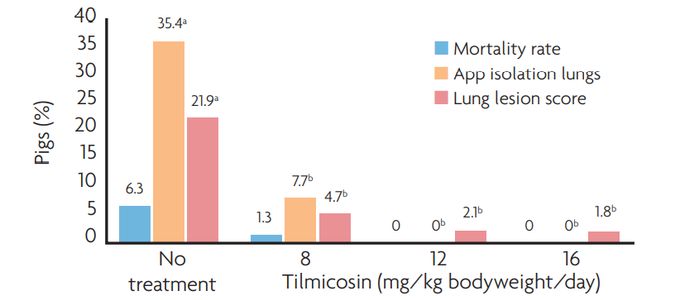

The minimal inhibitory concentration of tiamulin to inhibit growth of 90% (MIC90) of the M. hyopneumoniae strains tested is not more than 0.06μg/ml (Table 1).

This molecule does not only show an excellent absorption after oral administration and a low plasma protein binding capacity but also high tissue concentrations in the lung. The exposure to tiamulin is 18 times higher in lung tissue compared to plasma (Figure 2).

As the survival time of the pathogen outside the pig's body is reported to be short, a treatment duration of 14 consecutive days is advised. The daily dosage is 10mg tiamulin hydrogen fumarate per kg bodyweight. Special attention has to be paid to correct dosing, mainly for the sows in the lactation units. Sows refusing to eat are removed or injected with tiamulin for five consecutive days. If they still do not eat after injections, they should be removed from the herd.

The administration of the antimicrobial product is also efficacious for controlling several concurrent infections like ileitis, Brachyspira spp., Mycoplasma arthritis and bacterial pneumonia. This clearly contributes to the significant performance boost after the eradication programme.

- Continuation of farrowing even during the medication period. In this case, all the suckling pigs in the farrowing units are injected with a long acting product (tulathromycin 2.5mg/kg bodyweight) every four days, starting from one week before the start until the end of the medication programme of the sows.